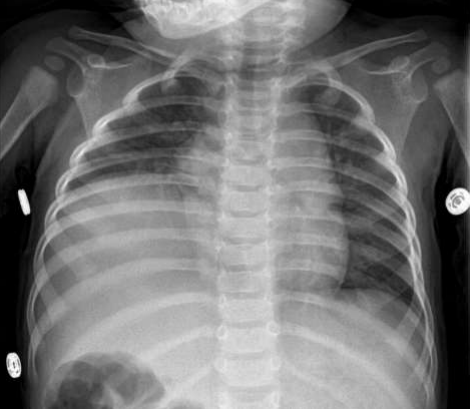

A paediatrics surgery consultation done, and the patient seen by paediatrics surgeon after five months and diaphragmatic repair done for the patient (Figure 5) with a subsequent clinical and radiological follow up which showed a significant ‘’CXR’’ findings improvement (Figure 6) with complete absence of the hiccup in the out-patient follow up with my clinic (Figure 7).

Figure 6: The post-operative chest-x-ray done for the patient in the PICU